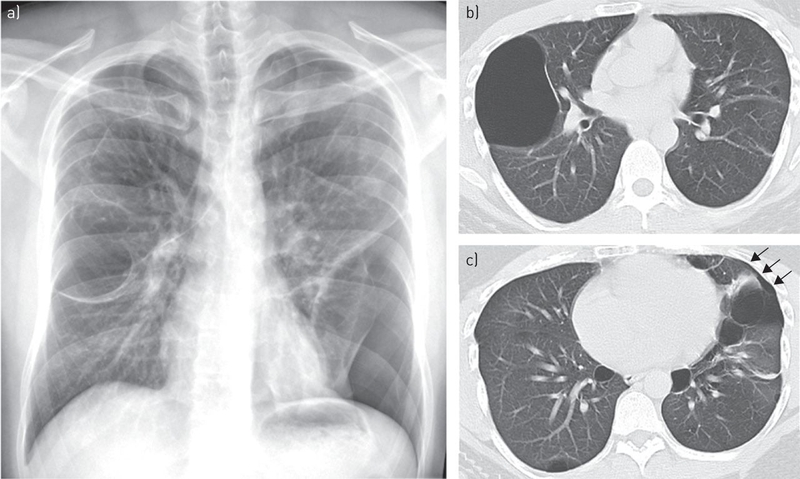

Sự tràn khí trong y học là hiện tượng không khí tràn vào các khoang trống trong cơ thể, cụ thể là các mô dưới da và có thể gây ra tràn khí trung thất, tràn khí ổ bụng hoặc nguy hiểm hơn là tràn khí màng phổi. Không khí khi xâm nhập được vào các khoang sẽ dẫn đến sự chênh lệch áp suất giữa lòng phế nang và những kẽ hở quanh mạch máu, khiến không khí lan đến đầu, cổ, ngực và bụng một cách nhanh chóng.

Không khí khi xâm nhập vào làn da có thể đi theo chiều của các vùng bao quanh mạch, đi đến trung thất và từ đó lan truyền đến hệ thống mô dưới da một cách nhanh chóng. Trong trường hợp tràn khí dưới da và có thể gây tình trạng phổi bị đâm thủng do chênh lệch áp suất. Tương tự như vậy, chênh lệch áp suất ở phổi cũng có thể khiến các phế nang bị phá vỡ, gây chấn thương và tràn khí màng phổi - một trong những biến chứng nguy hiểm nhất của tràn khí dưới da.